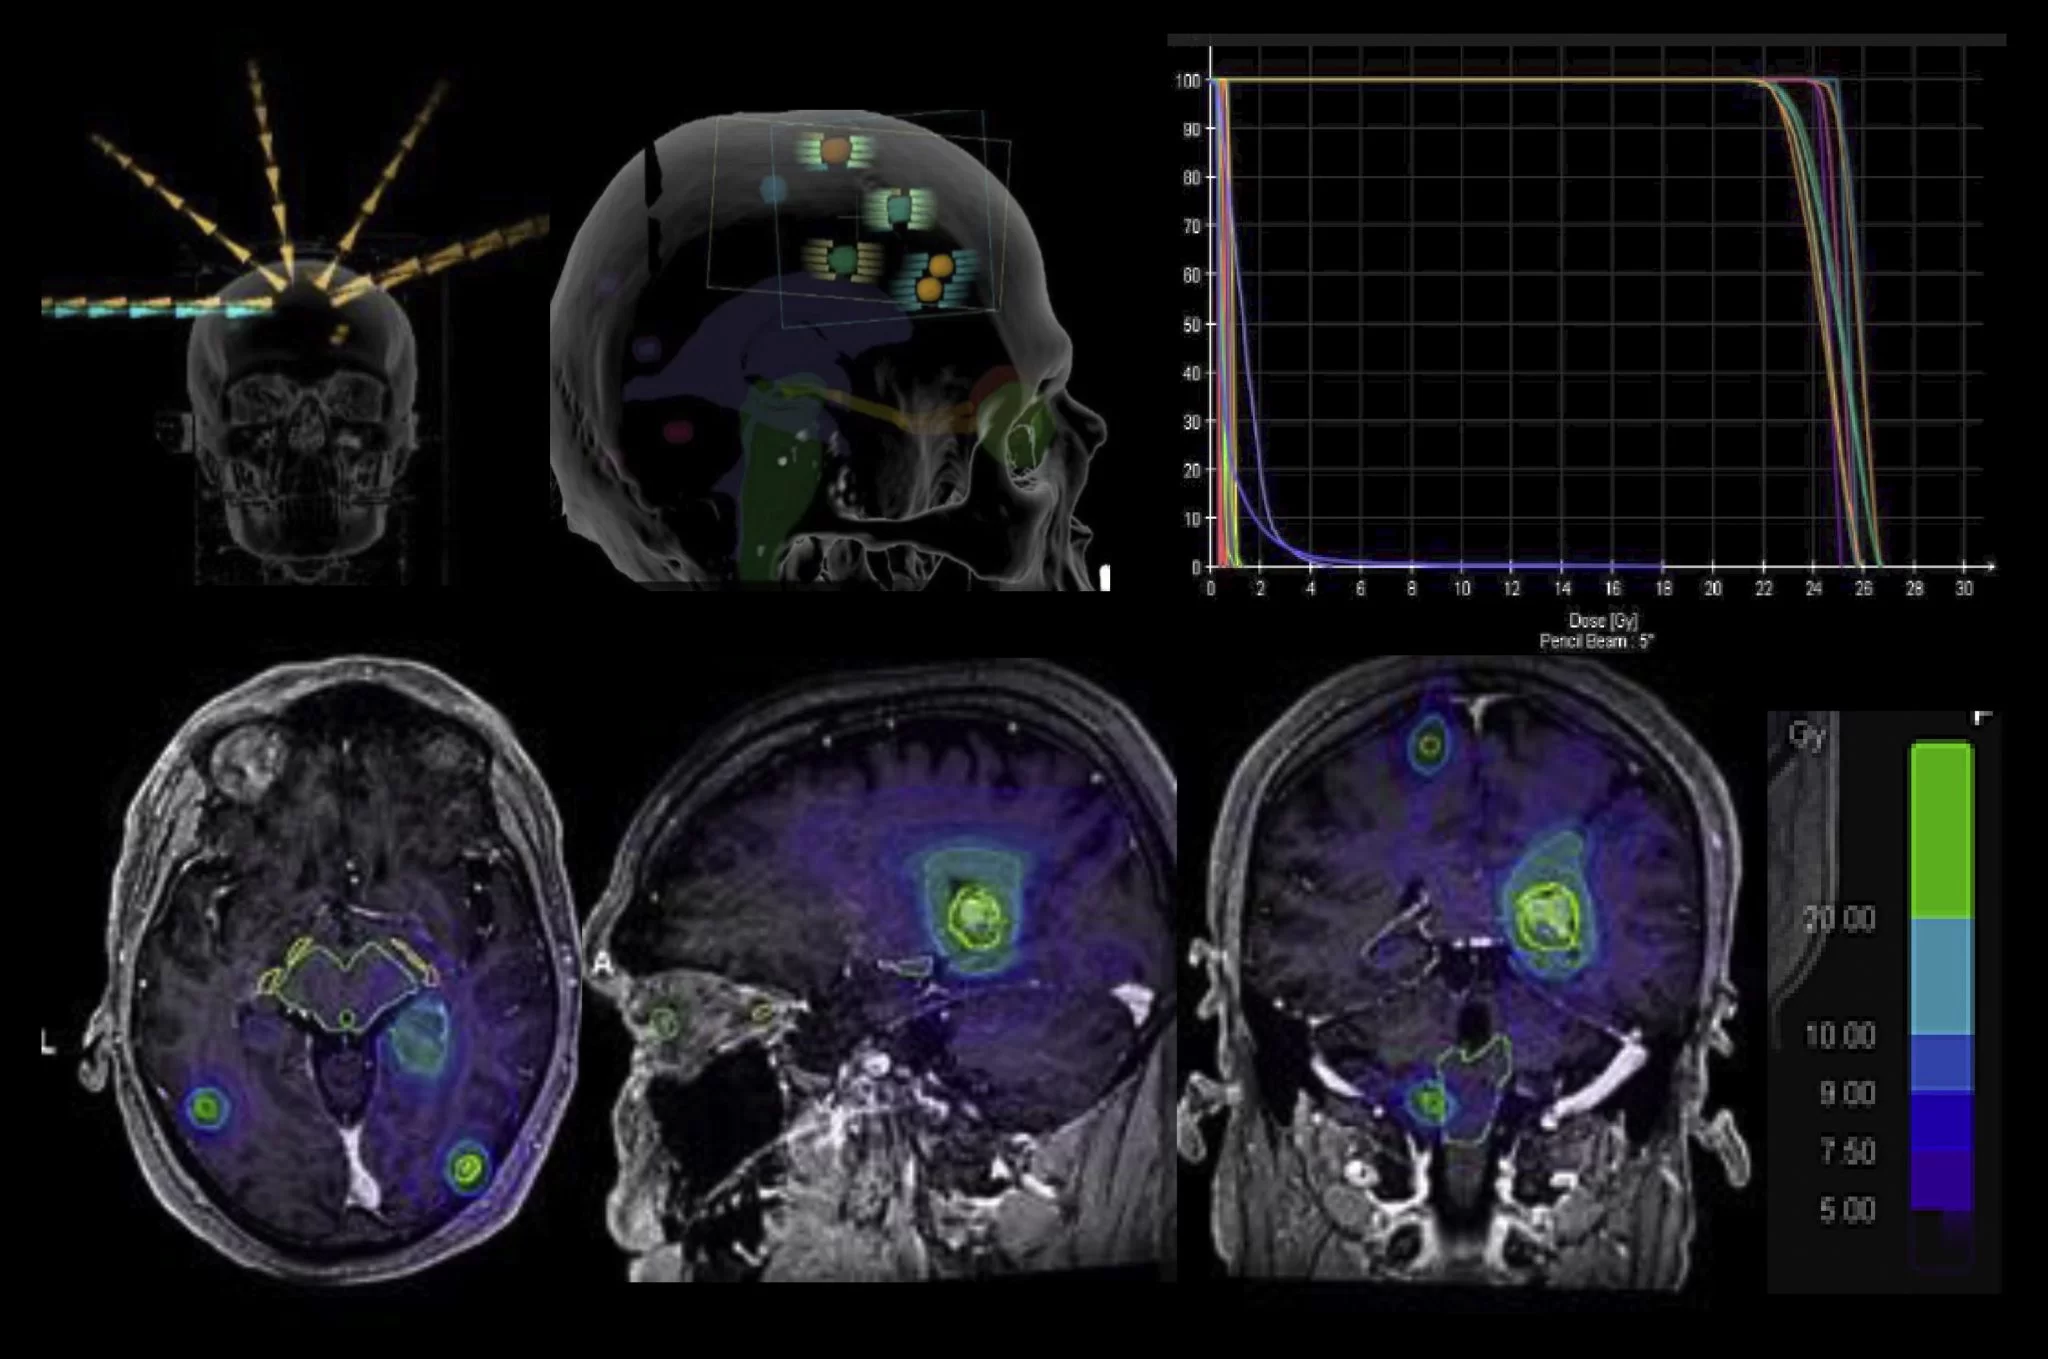

Radiochirurgie stereotactica (SRS) pentru metastaza cerebrală

Radiochirurgia stereotactică (SRS) nu este o intervenție chirurgicală. Este o doză mare de radiații la locul tumorii, administrată într-un mod foarte precis.

Capul tău trebuie să fie ținut foarte nemișcat folosind o cască sau o mască, astfel încât să nu te miști în timpul tratamentului. Metastazele tratate cu SRS ar trebui să fie de 3 cm sau mai mici.

SRS se administrează într-o singură doză (Gamma Knife®) sau până la cinci doze (Cyberknife®). Mai mult de un creier întâlnit poate fi tratat în timpul unei sesiuni. De exemplu, dacă aveți 2 metastaze cerebrale separate, ambele ar putea fi tratate în aceeași zi.

Tratamentele sunt efectuate de o mașină tradițională de radiații numită accelerator liniar sau de o mașină specializată, cum ar fi Gamma Knife®, Cyberknife®, XKnife® și ExacTrac®.

Gamma Knife® furnizează câteva sute de fascicule de radiație dintr-o sursă de cobalt. Fasciculele de radiație se concentrează în punctul în care toate fasciculele se întâlnesc (vezi imaginea).

Fasciculele de radiație traversează sute de găuri ale căștii. Acest lucru permite ca o doză mare de radiație să fie livrată tumorii, protejând în același timp țesutul din jur de doza mare.

XKnife® este un tratament pe bază de accelerator liniar. La fel ca Gamma Knife, se folosește un cadru pentru cap, care va rămâne aprins pe tot parcursul tratamentului.

Cyberknife® este o formă de SRS fără cadru care utilizează un accelerator liniar miniatural specializat cu un braț robot. În loc să folosiți un cadru pentru a vă menține nemișcat, se folosește o mască personalizată pentru fiecare pacient împreună cu urmărirea bazată pe craniu, permițând robotului să urmărească o țintă.

Cyberknife® poate trata, de asemenea, leziuni mai mari de 3 cm și poate fi utilizat în alte părți ale corpului.

Terapia cu protoni este o formă mai nouă de SRS. În loc să folosiți fotoni pentru a ținti un met, protonii sunt folosiți pentru a viza un met. O mașină numită sincrotron sau ciclotron accelerează protonii, care sunt particule încărcate pozitiv.

Energia mare a acestor protoni în mișcare poate ucide celulele canceroase. În timpul tratamentului, protonii pot viza cu precizie tumora. Terapia cu protoni este un domeniu în creștere al terapiei cu radiații.